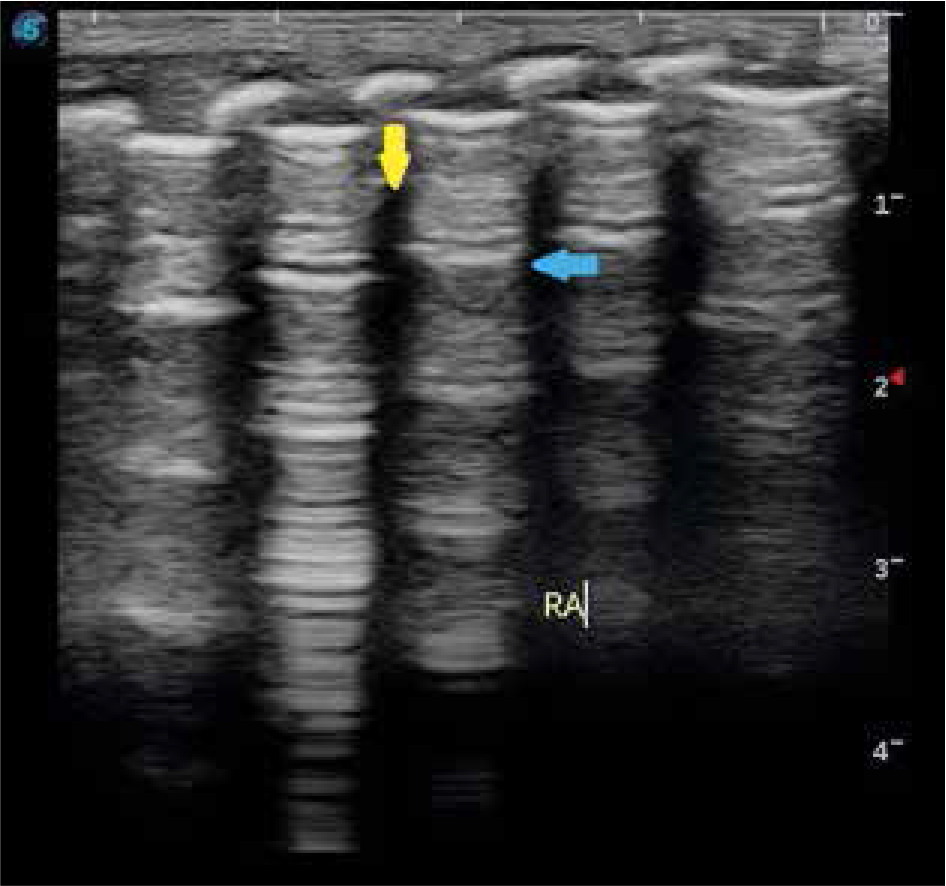

Figure 2

Longitudinal view of left posterior lung field with the arrow showing double lung point sign